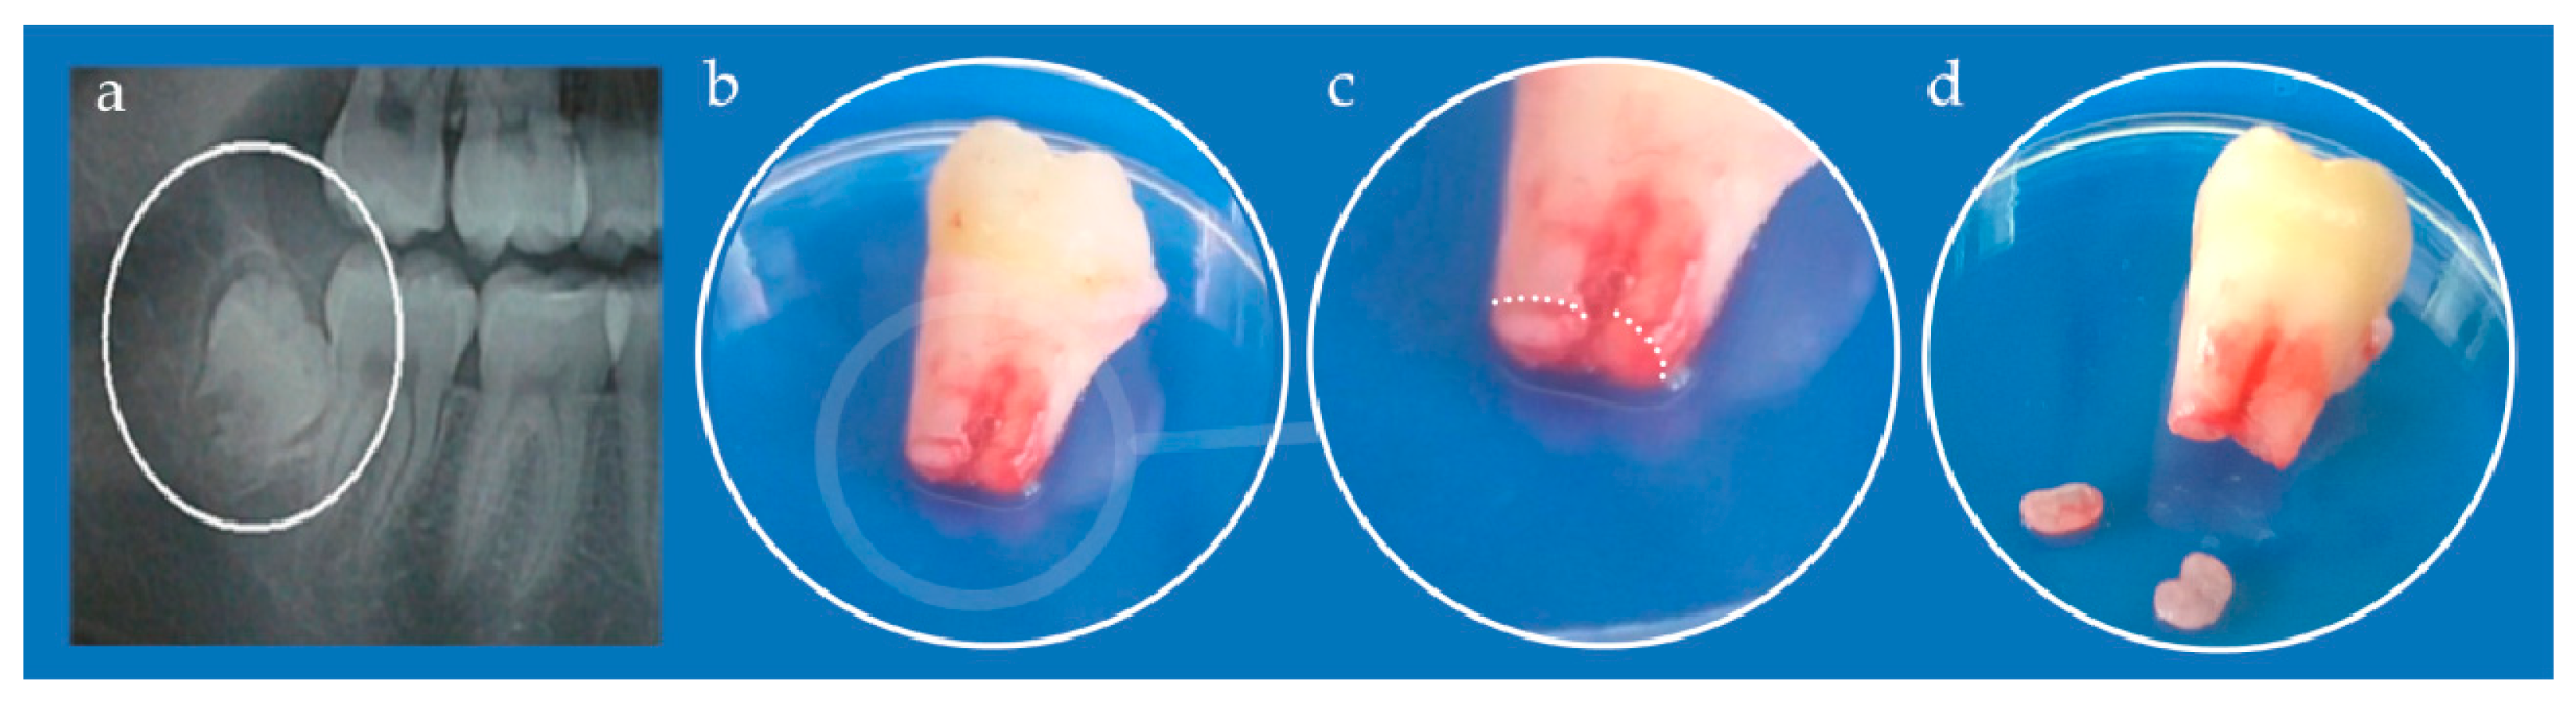

The study was approved by the Ethical Committee of the School of Dental Medicine, University of Belgrade (No 36/19). Immature, impacted third lower molar was extracted from a teenage patient at the Clinic for Oral Surgery (Figure 3), School of Dental Medicine, University of Belgrade, after signing the informed consents by patient’s parents. Stem cells from apical papilla were isolated as previously described [34]. Briefly, extracted tooth was rinsed with Dulbecco’s Phosphate-Buffered Saline (DPBS, Thermo Fisher Scientific, Waltham, MA, USA), and apical papilla was separated from the root apex and transferred into T-25 flasks after mincing. The tissues were grown in cell complete medium (DMEM supplemented with 10% fetal bovine serum and 1% antibiotic-antimycotic solution). Cells were cultured under standard conditions (37 °C, 95% air–5% CO2 atmosphere, 95% humidity) and growth medium was changed every third day. All following experiments were carried out with the cells from the fourth and fifth passage.

Figure 3. (a) Orthopantomogram of right mandibular impacted third molar (encircled); (b) Extracted tooth; (c) Detail from (b) white dotted line depicts border between apical papilla (lower parts) and tooth root (upper part); (d) Kidney-shaped apical papilla tissues separated from the tooth.